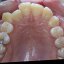

Ortodonzia Linguale Classica

» Immagine 6/9